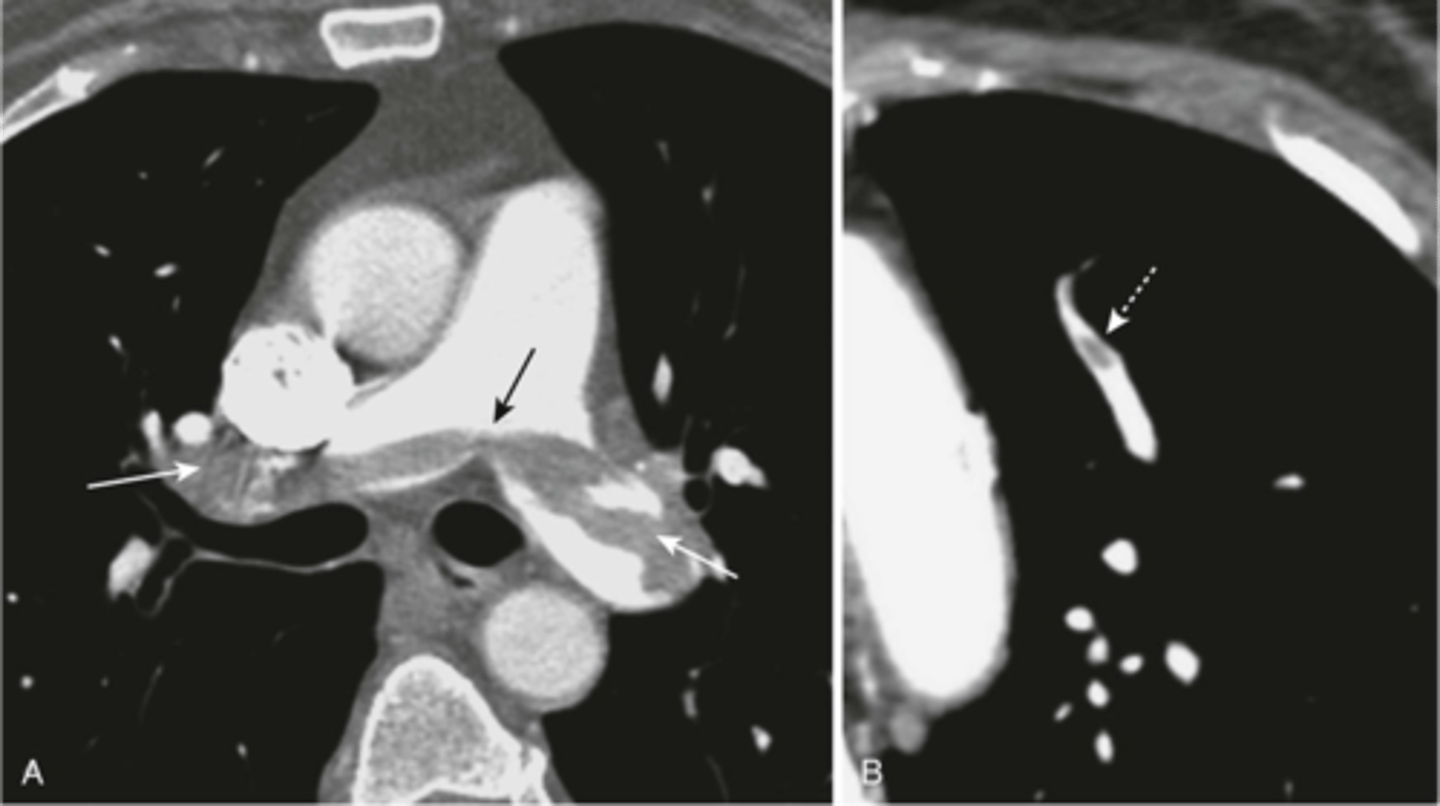

-embolus fills both pulmonary arteries (left side)

-right picture is a small embolus

How does a saddle embolus appear